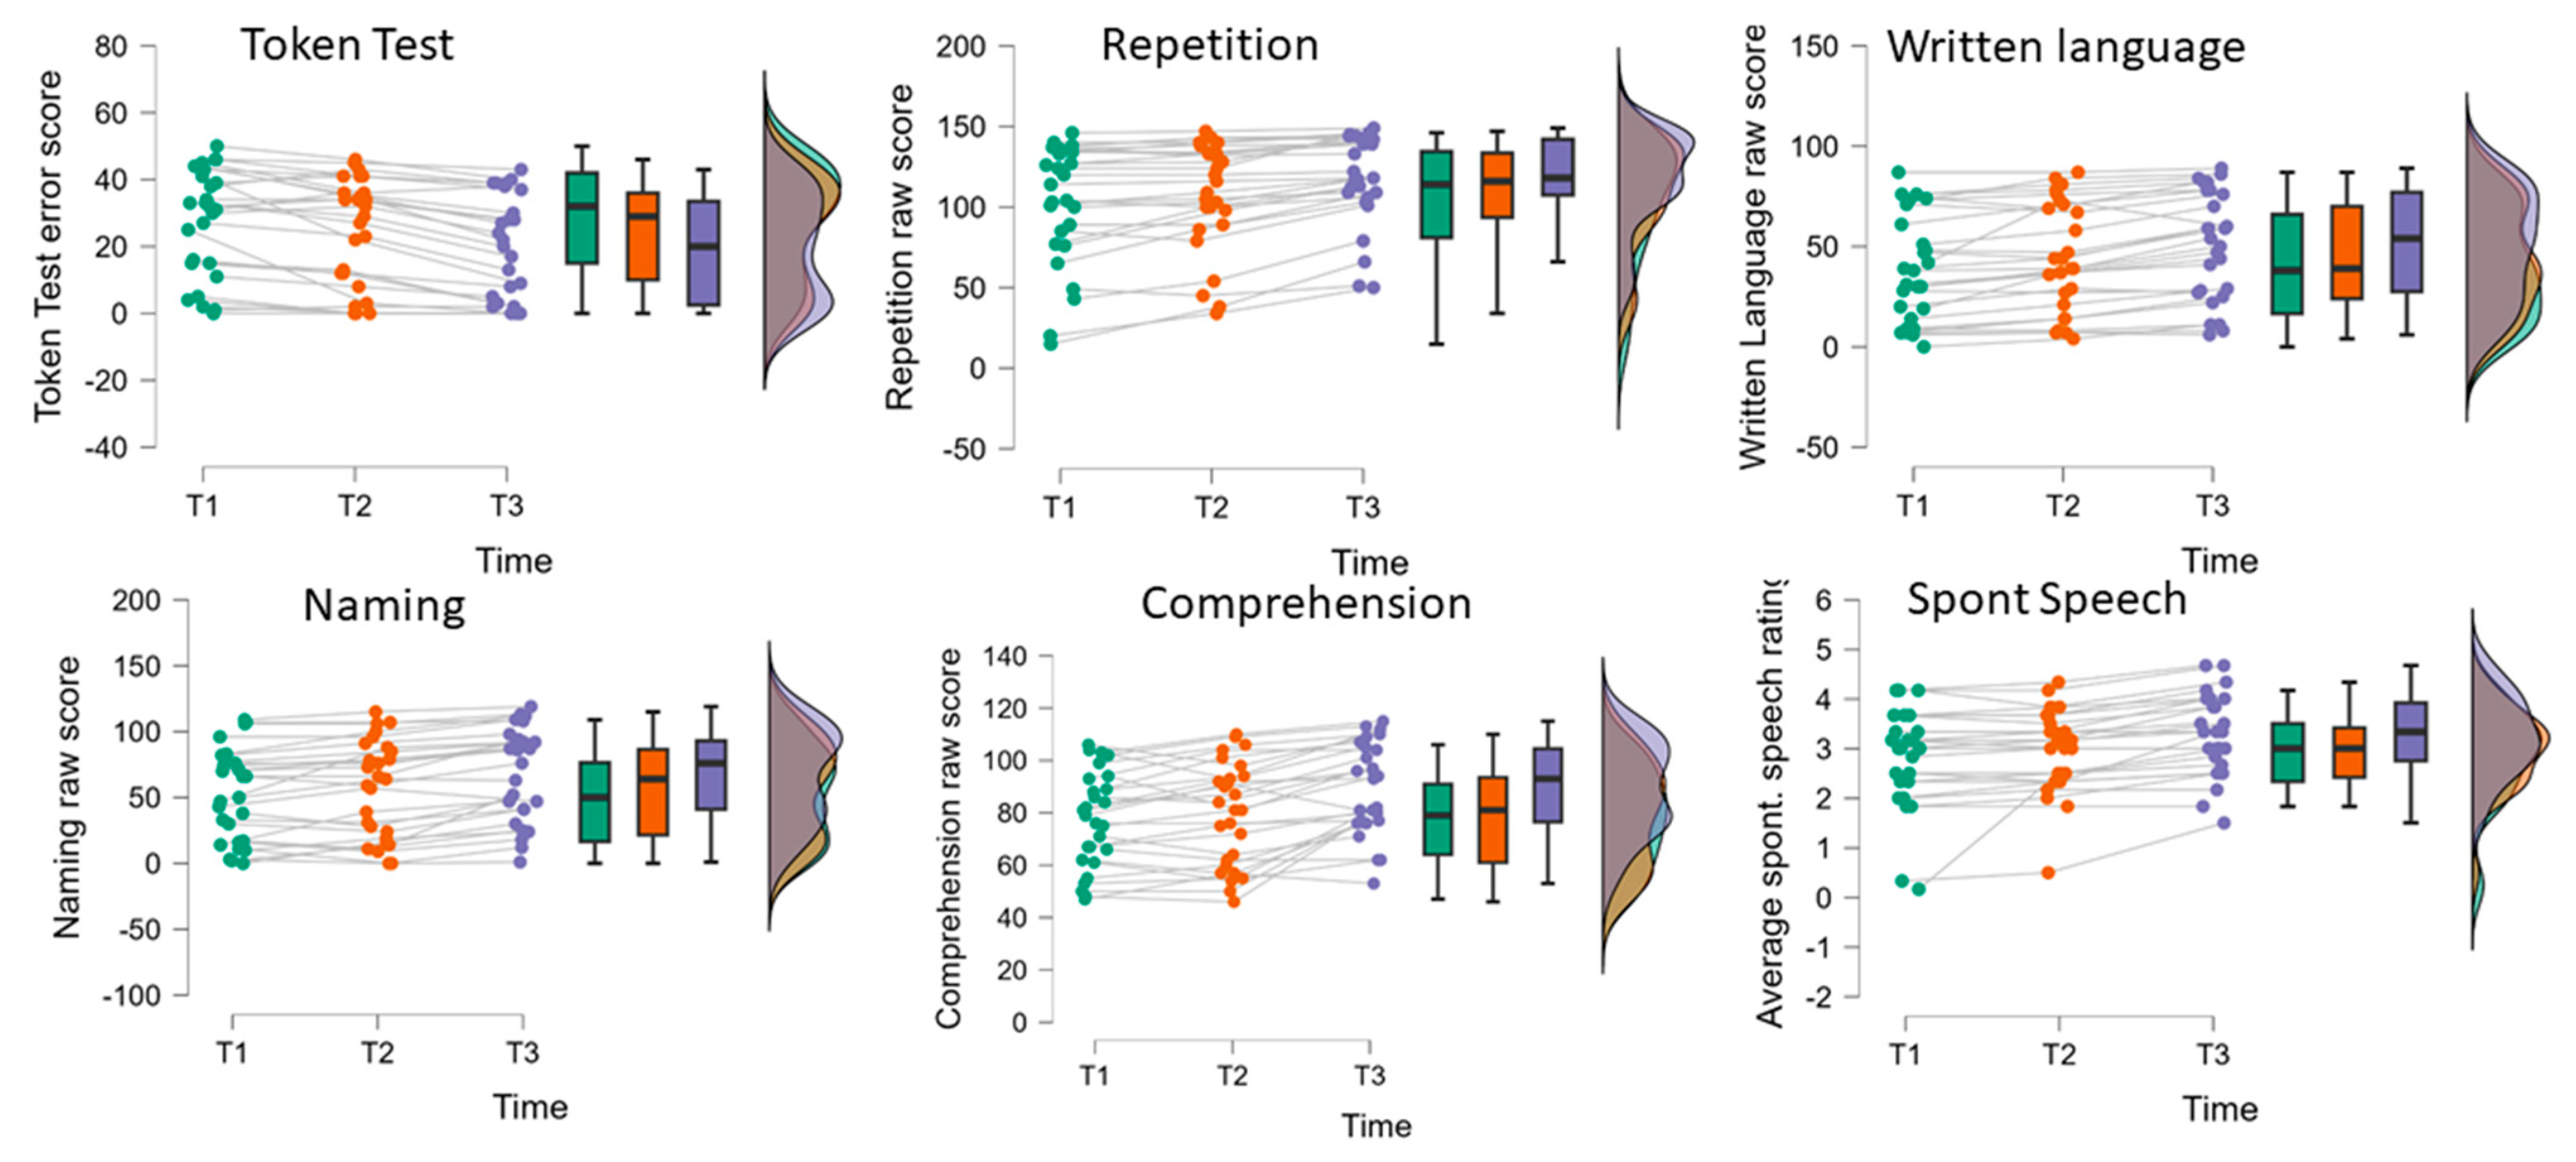

| A | AAT | T1 | T2 | T3 | ANOVA Factor Time | Post Hoc Compar. § | ||

| (n = 27) | M (SD) | M (SD) | M (SD) | F(2,52) # | p | η2p | ||

| Profile level (T-norm) | 49.60 (7.02) | 51.04 (7.50) | 54.10 (8.50) | 63.97 | <0.001 | 0.71 | T1 < T2 < T3 | |

| Spont. | Ave. spont. speech rating | 2.83 (1.91) | 2.95 (0.82) | 3.27 (0.82) | 14.08 | <0.001 | 0.35 | (T1,T2) < T3 |

| TT | Token Test (errors) | 27.78 (16.10) | 24.04 (16.24) | 19.00 (15.67) | 25.37 | <0.001 | 0.49 | T1 < T2 < T3 |

| REP | Repetition | 102.70 (37.80) | 107.82 (33.68) | 117.82 (28.77) | 26.98 | <0.001 | 0.51 | T1 < T2 < T3 |

| WRIT | Written language | 39.44 (26.68) | 44.34 (26.76) | 50.56 (26.85) | 33.64 | <0.001 | 0.56 | T1 < T2 < T3 |

| NAM | Naming | 51.74 (35.04) | 56.70 (36.71) | 67.15 (35.39) | 25.41 | <0.001 | 0.49 | T1 < T2 < T3 |

| COMP | Comprehension | 77.33 (18.30) | 79.59 (19.66) | 89.11 (17.44) | 26.64 | <0.001 | 0.51 | (T1,T2) < T3 |